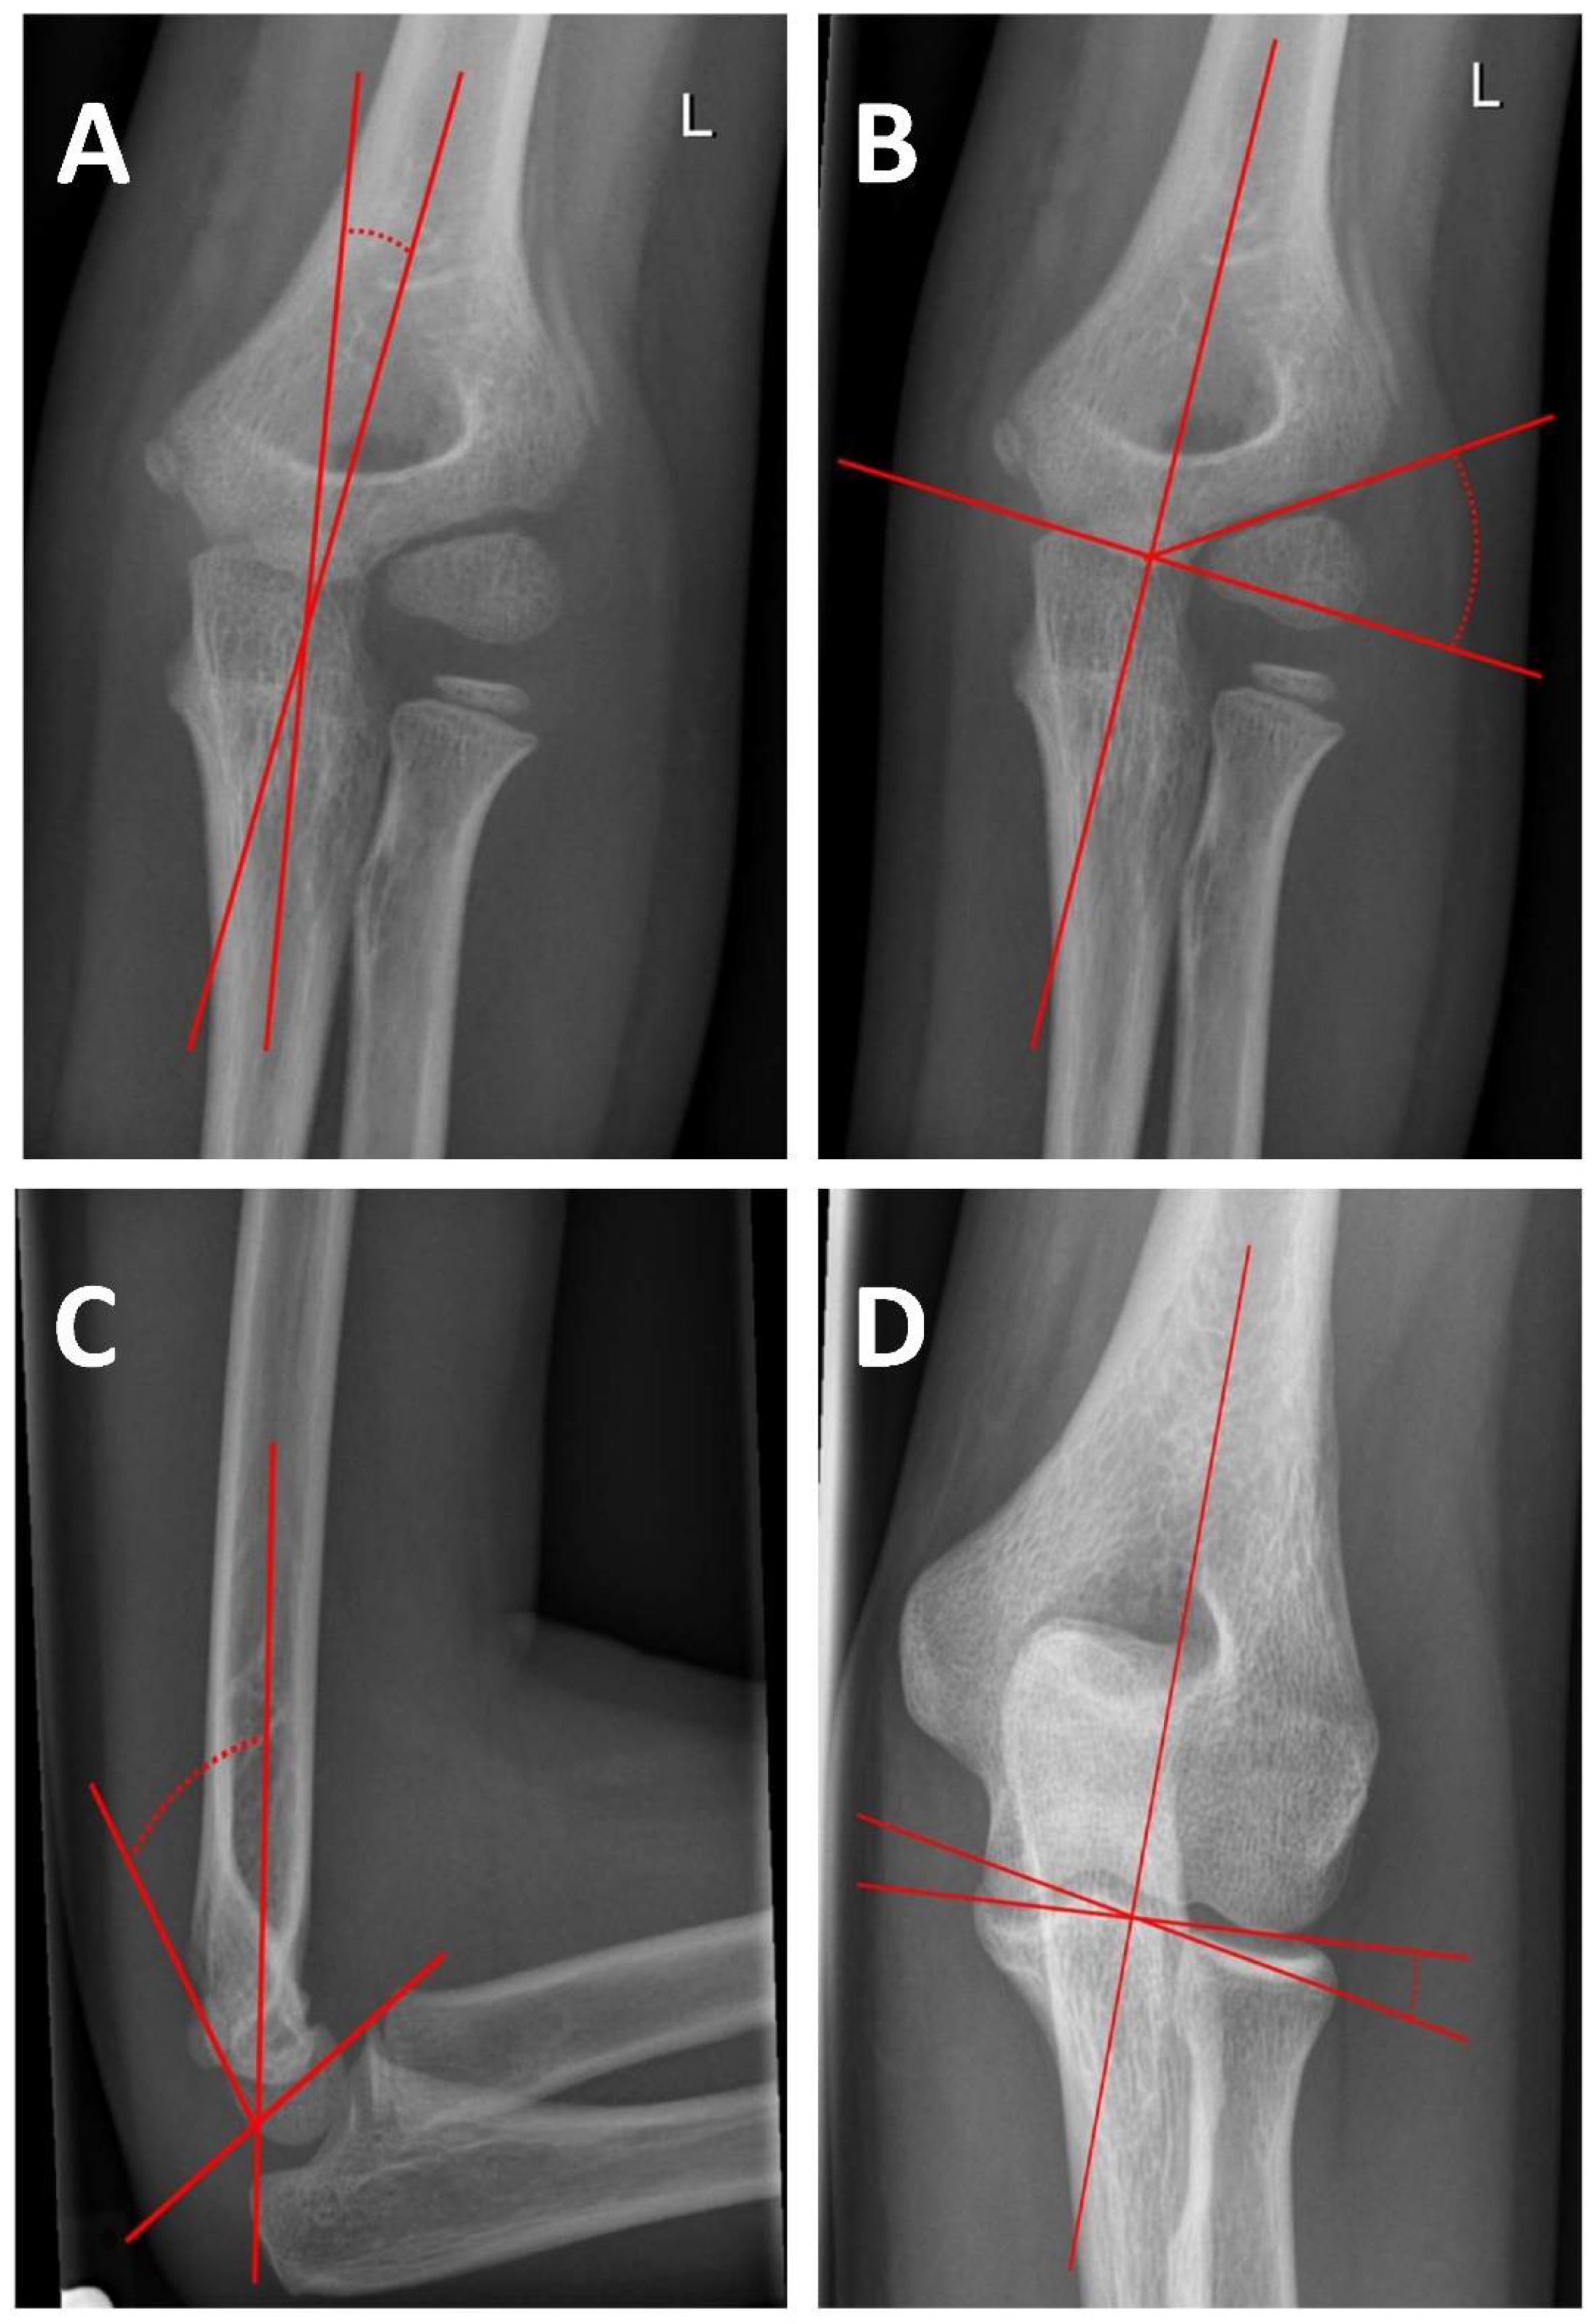

Humeral Ulnar Angle

Baumann’s Angle

Antecurvation Angle

Humeral Trochlear Angle